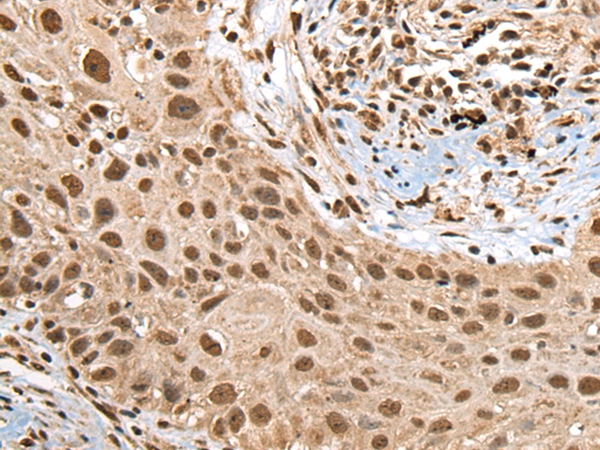

The image on the left is immunohistochemistry of paraffin-embedded Human lung cancer tissue using 46662(RTCB Antibody) at dilution 1/45, on the right is treated with fusion protein. (Original magnification: x200)

The image on the left is immunohistochemistry of paraffin-embedded Human prostate cancer tissue using 46662(RTCB Antibody) at dilution 1/45, on the right is treated with fusion protein. (Original magnification: x200)